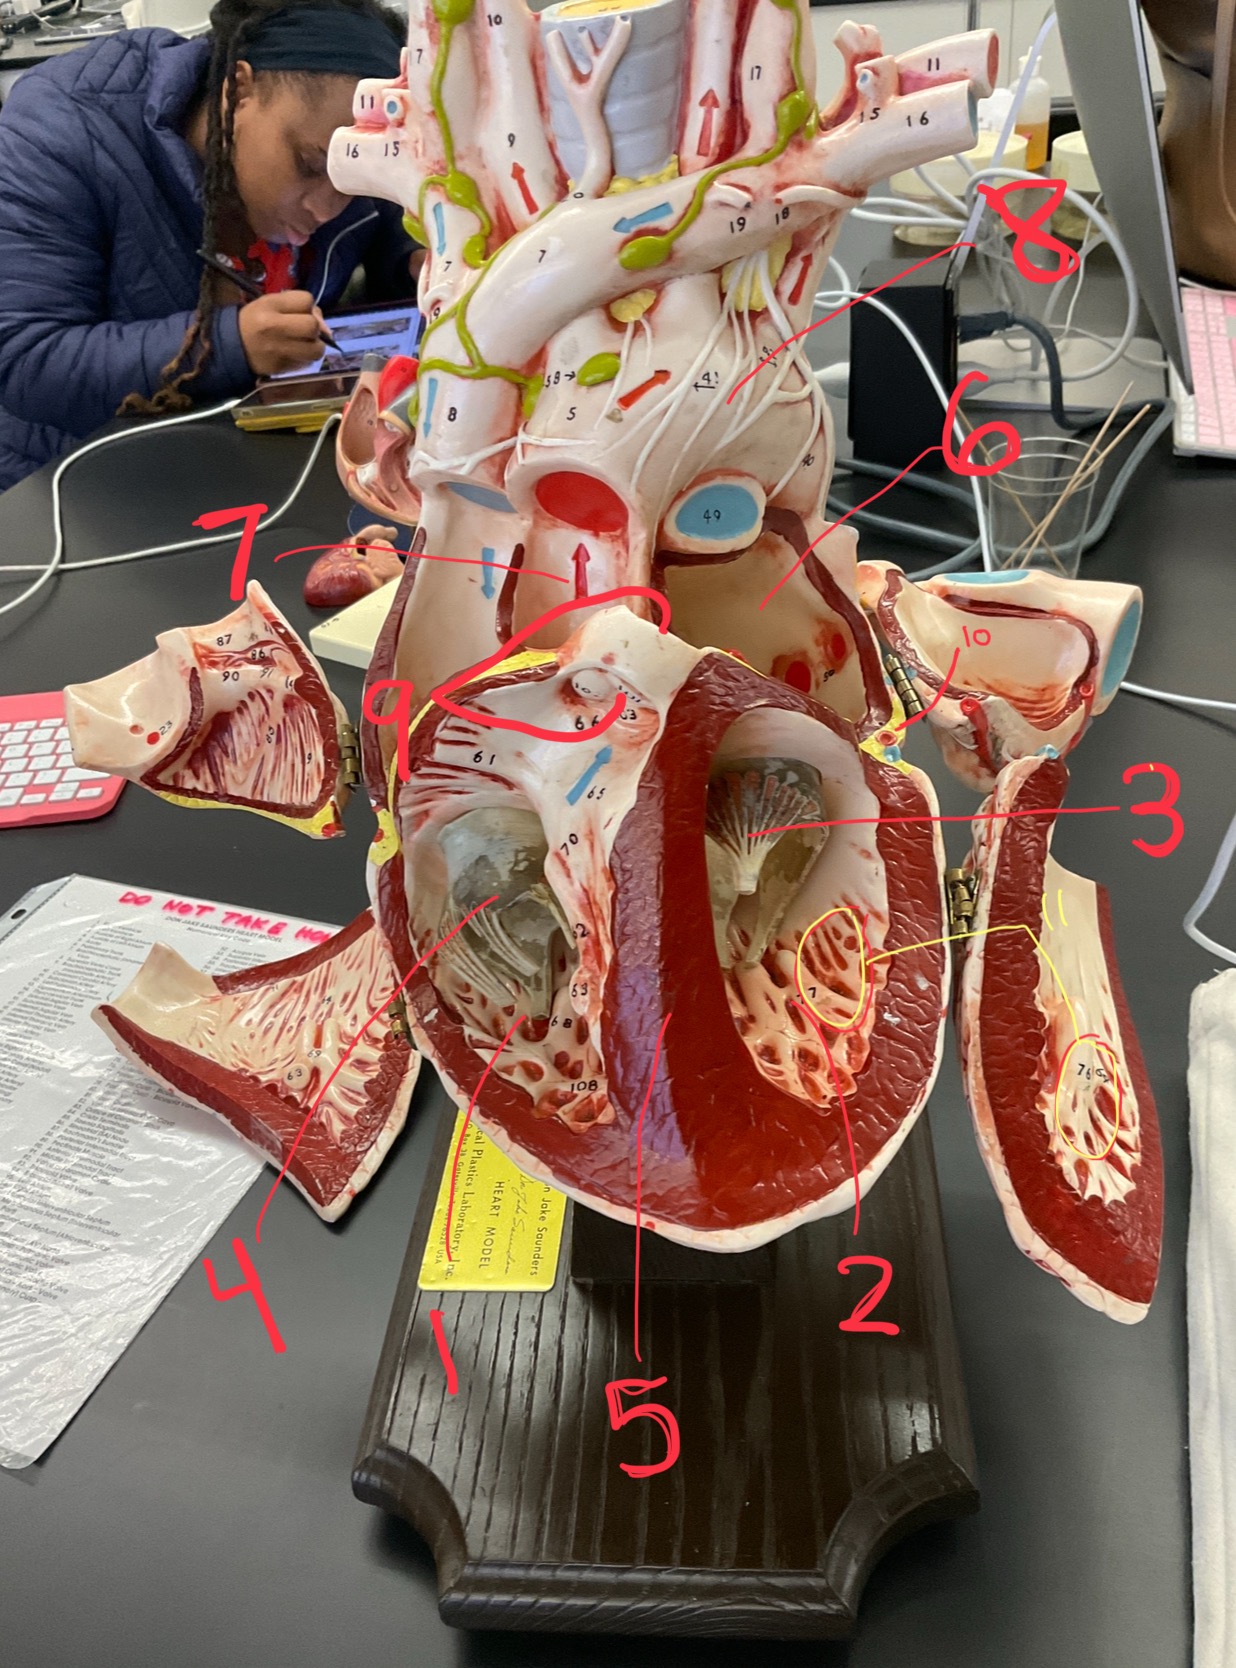

1

epicardium

2

3

endocardium

3

2

myocardium

4

1

coronary sinus

5

2

inferior vena cava

6

3

superior vena cava

7

1

right ventricle

8

2

left ventricle

9

3

bicuspid

10

4

tricuspid

11

5

interventricullar septum

12

6

left atrium

13

7

aorta

14

8

aortic trunk

15

9

pulmonary semi-lunar valve

16

10

atrevoventricullar sulus

17

11 (not smooth part)

trubeculae carneae

18

1

papillary muscle

19

2

chordae tendineae

20

4

pulmonary trunk

21

6

aortic trunk